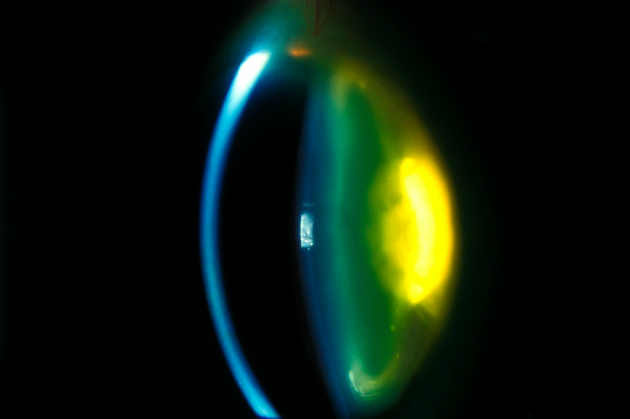

Теперь же учёные из Университета Осаки и Кардифского университета смогли использовать стволовые клетки человека для воспроизведения всей сложной природы глазного яблока. С помощью индуцированных плюрипотентных стволовых клеток (то есть клеток, полученных непосредственно из клеток взрослого организма, а затем обращённых в «детство») исследователи смогли вырастить несколько клеточных копий глаза, в том числе хрусталик, роговицу и конъюнктиву.

Ткани были пересажены кроликам и макакам с искусственно созданной роговичной слепотой, в результате чего зрение было восстановлено. Команда утверждает, что это достижение вскоре может привести клиническим испытаниям подобных трансплантатов для восстановления утерянного зрения и у людей.